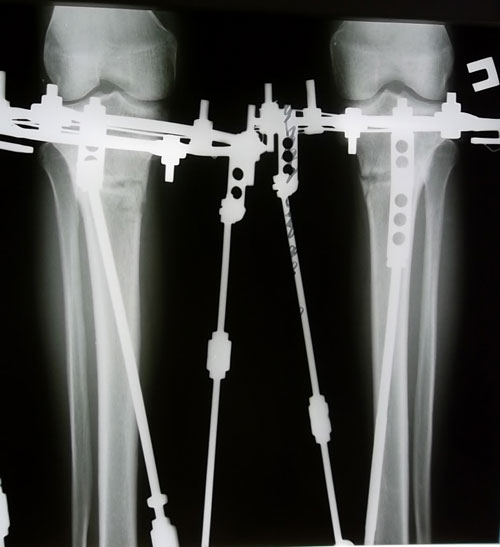

Рентген 2 месяца с момента операции.

Вложения

SAM_3807.JPG

SAM_3805.JPG